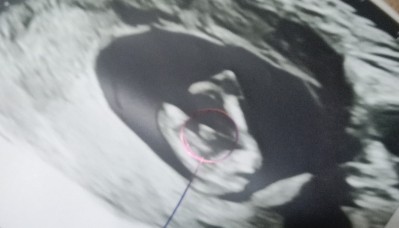

12 hafta 6 günlükken doktor cinsiyetini söyledi işaretleyip yazdı ama herkes kafamı karıştırdı yanilabilir felan dedi

Benim attığım bacak arasiyla benziyormu canim

Banada 12 hafta 6 günlük  kesin emininim cinsiyeti belli soylleyimmi dedi yüzde kaç hocam dedim yüzde yüz erkek dedi de çevremdekiler yanilabilir diyince şüpheye düştüm